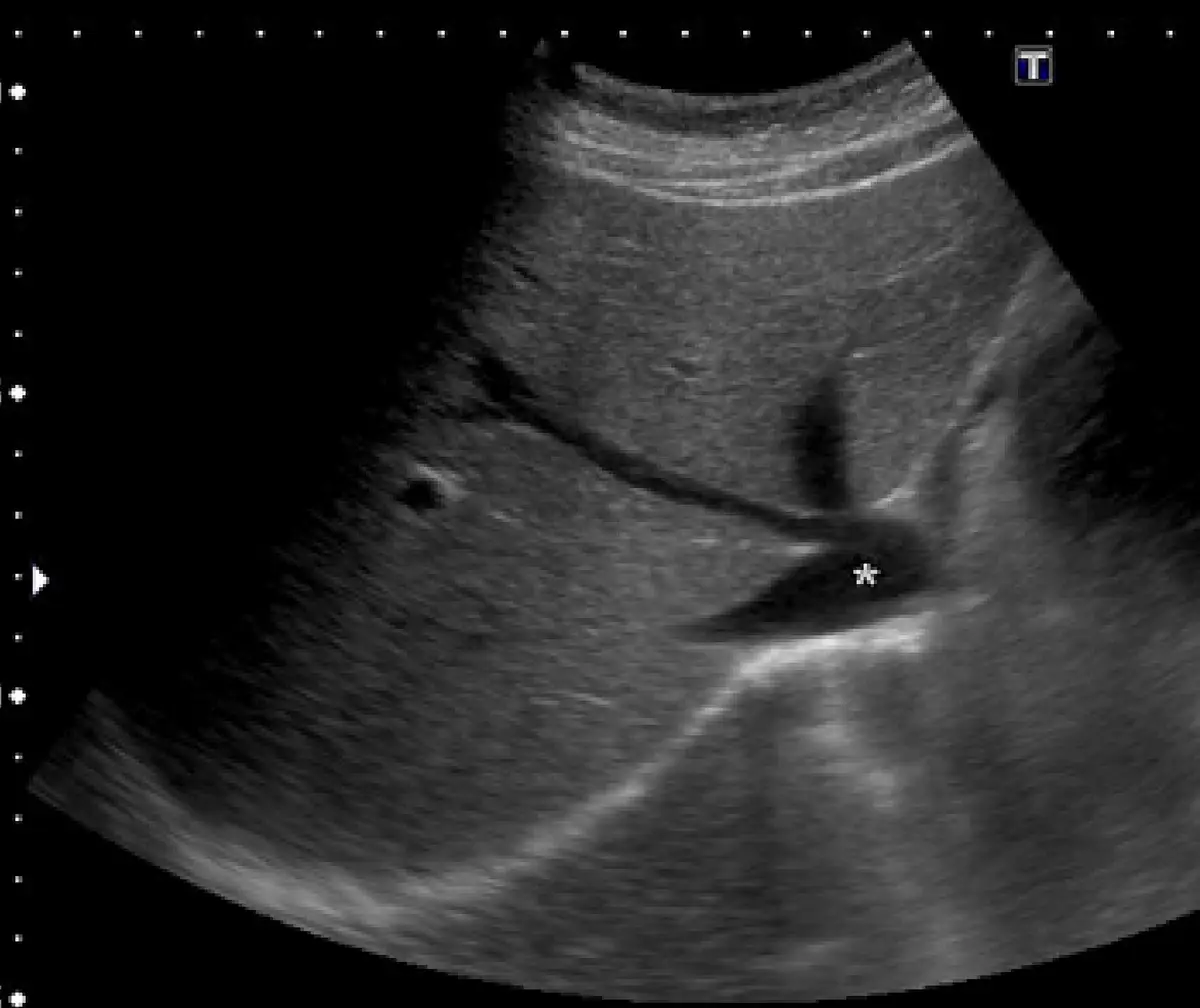

下圖 為腹部超⾳波的影像,圖中星號所指為何?

影像為右側肋下或右肋間斜切面的腹部超音波圖,視野中可見大範圍肝臟實質(灰色均勻回聲)。星號(*)標記的結構位於影像右側偏後下方、肝後間隙處,呈橢圓形無回聲(anechoic)管狀結構,管壁薄而稍有回聲,形態與下腔靜脈(IVC)一致。

- 位置:位於脊柱右前方、肝後方,為 IVC 的標準走行位置(腹主動脈位於脊柱左前方)

- 形態:管壁薄(IVC 為薄壁靜脈),呈橢圓形橫切面

- 無門脈特徵:門靜脈(portal vein)位置較前,且門靜脈壁有高回聲的纖維組織包圍(portal tracts),與 IVC 可區別

- 無搏動增強回聲:腹主動脈呈圓形、管壁較厚、具有明顯搏動,可排除

- 上腔靜脈(superior vena cava, SVC):位於胸腔內,腹部超音波無法見到,可直接排除

(A) 下腔靜脈 — 正確。影像星號所指之無回聲管狀結構,位於肝後偏右側、脊柱右前方,為 IVC 的典型超音波表現。IVC 在此切面常呈